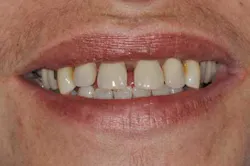

Fig. 2: Anterior teeth relationships prior to treatment

A 40-year-old woman, with no medical history except that she is a smoker (five cigarettes a day), is visiting us for an oral rehabilitation. Her chief complaints are teeth mobility and an esthetic concern since her maxillary front teeth are moving forward. The patient also suffers from dental anxiety.

The patient’s main problem is adult aggressive periodontitis, aggravated by tobacco use. The consequent tooth losses have caused migrations of the remaining teeth under functional adaptation.